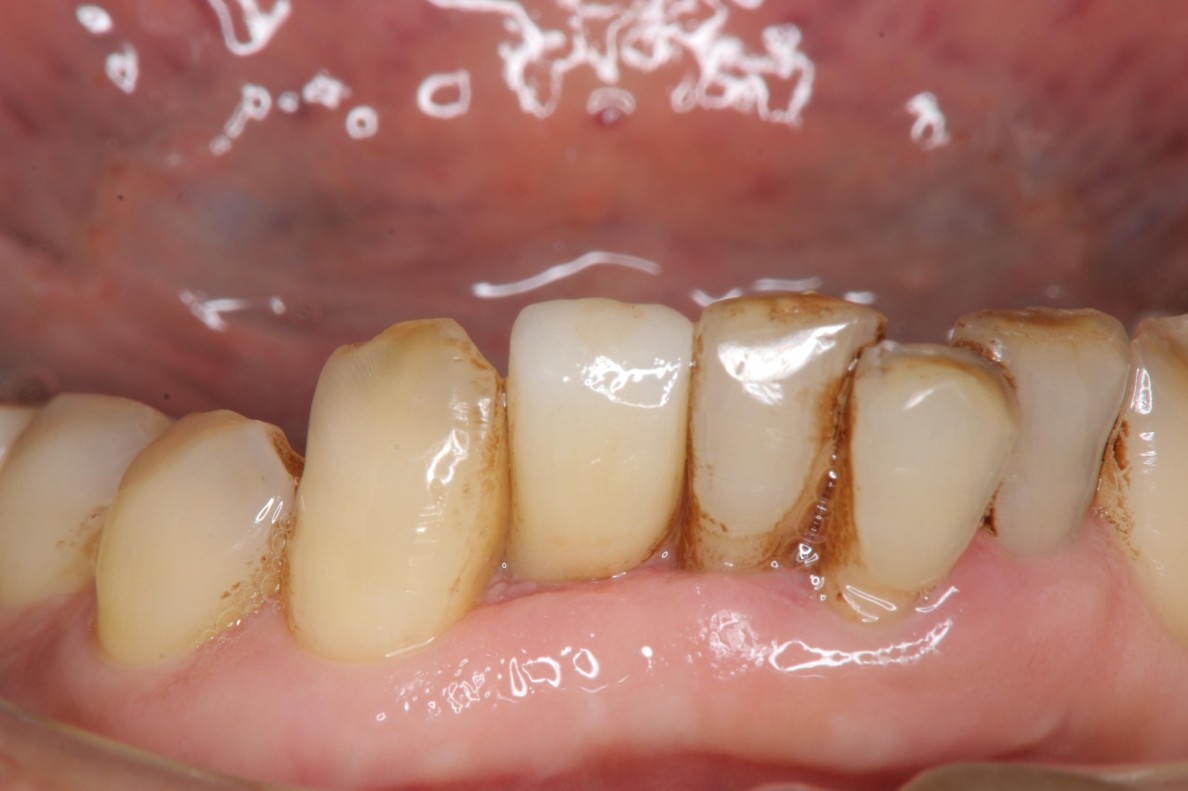

治療後,咬合牙周適應良好

治療後,密合度良好